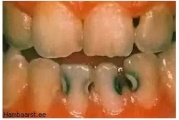

Lutipudelikaaries

Lutipudelikaariese kahjustused